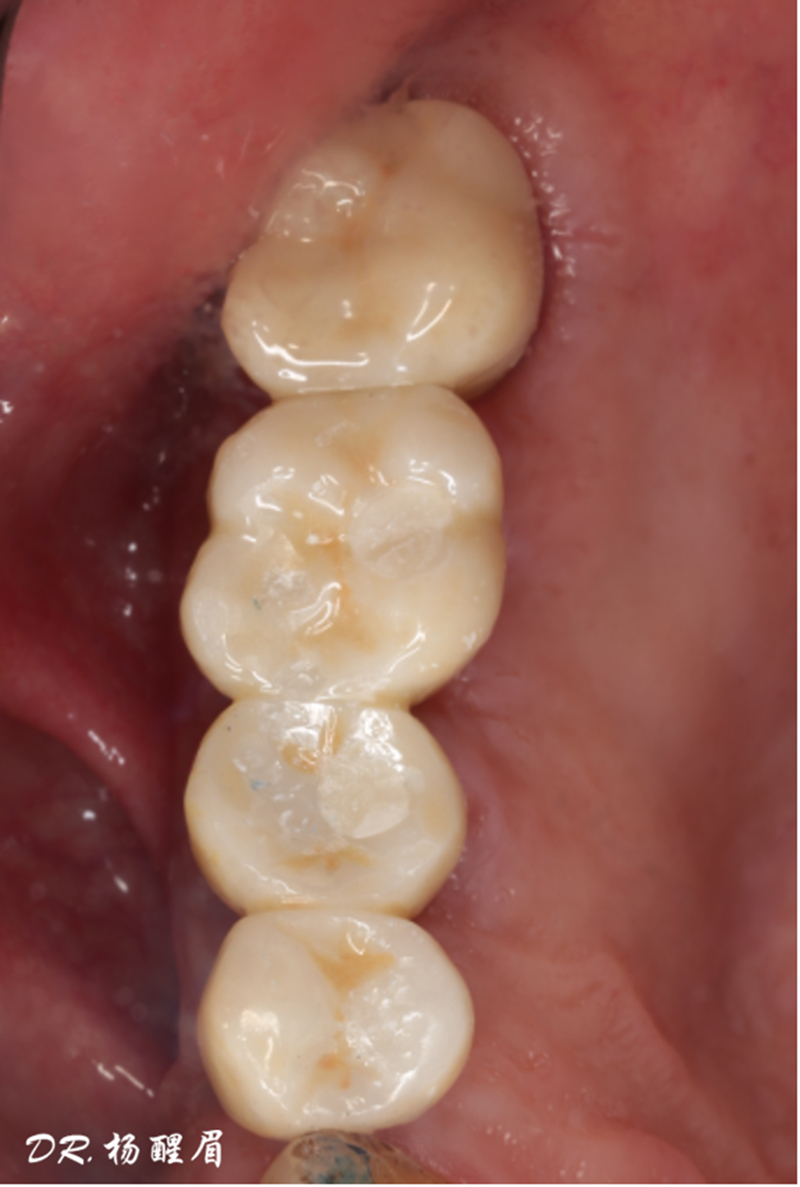

修復完成

®袖口形態(tài)

®基樁形態(tài)